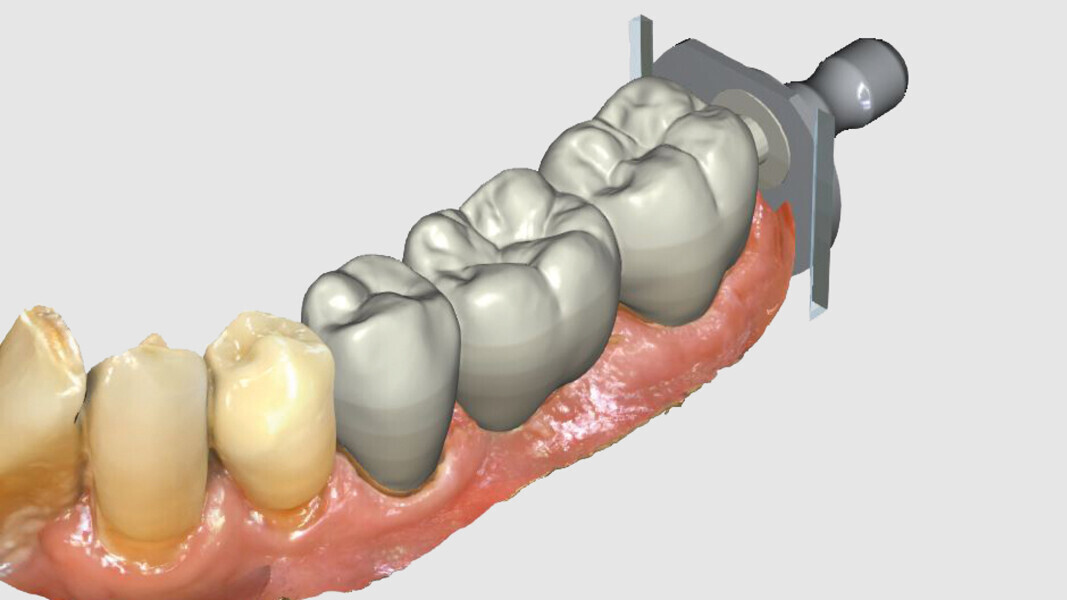

Fig. 4: Bridge design using CEREC Software.

Fig. 5: Bridge design using CEREC Software.